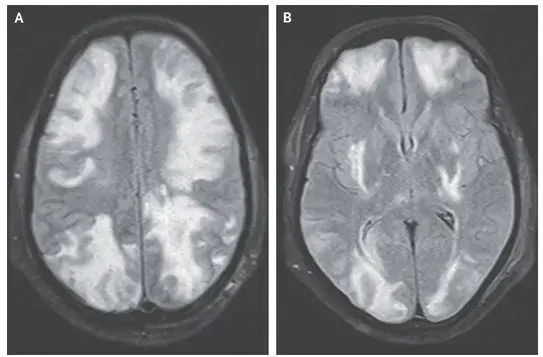

Cefaleia, alteração visual e convulsão em um paciente com nefropatia por IgA

Caso clínico publicado no NEJM: Um homem de 35 anos com nefropatia por IgA procurou pronto-socorro com quadro de confusão mental, visão embaçada e convulsão há 01 dia. Duas semanas antes da apresentação ele começou a tomar ciclosporina para tratamento de nefropatia por IgA. Sua PA era de 160/80 mm Hg. Ao exame físico paciente